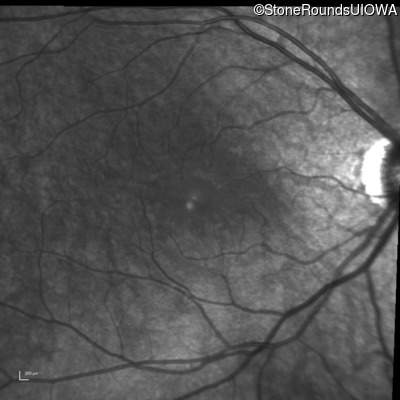

Infrared Fundus Photograph - Left - 20/50

Exemplar